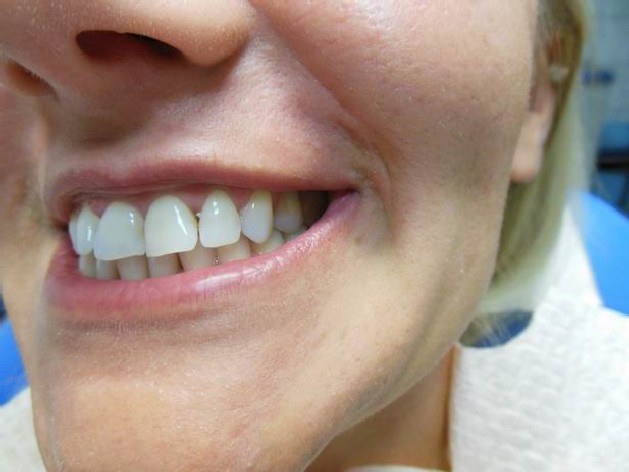

Ortodoncja CBCT

Leczenie chirurgiczno-ortodontyczne wad zębowych z zastosowaniem tomografii spiralnej CBCT w naszej klinice.